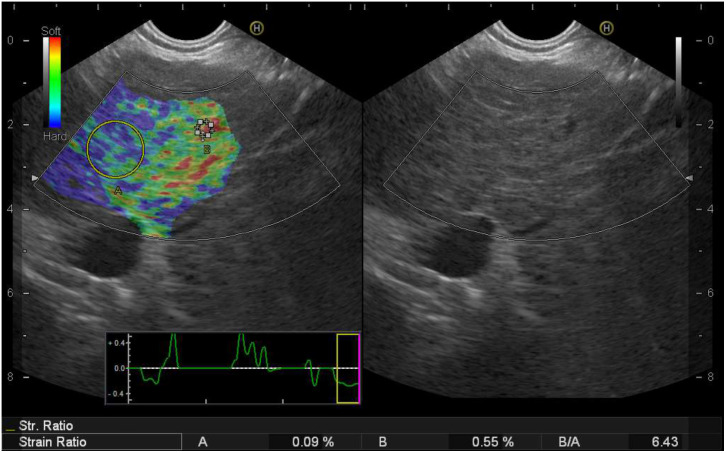

Background/Aims: The role of semi-quantitative strain ratio (SR) using real-time endoscopic ultrasound strain elastography (EUS-E) in chronic liver disease (CLD) and cirrhosis is yet to be determined. Herein, the aim was to assess the usefulness of EUS-E to detect CLD and cirrhosis. Materials and Methods: Patients with cirrhosis and non-cirrhotic CLD were enrolled prospectively. Patients without liver disease and undergoing EUS examinations for non-hepatic indications were taken as control group. Strain ratio was calculated from strains of hepatic vein and liver parenchyma. Fibrosis-4 (FIB-4) and aspartate aminotransferase (AST)-to-Platelet Ratio Index (APRI) scores were recorded, and blood cytokeratin-18 (CK-18) levels were measured to assess hepatic fibrosis. A clinical evaluation was also conducted. Results: One hundred participants (control: 49, CLD: 33, cirrhotic: 18) were included. The SR and liver parenchyma strains in cirrhotics were significantly higher than those in the CLD (P < .001) and control (P < .001) groups. Strain ratio threshold set at 5.67 had a sensitivity of 94.4% and a specificity of 95.9% to differentiate cirrhotics from control patients. An SR threshold of 10.65 had a sensitivity of 94.4% and a specificity of 84.8% in differentiating cirrhotics from CLD patients. The SR showed a strong positive correlation with FIB-4 and APRI scores, but not with CK-18 levels. Conclusions: Strain ratio thresholds of 5.67 and 10.65 obtained by EUS-E are useful to differentiate cirrhotics from non-cirrhotic CLD patients and liver-disease-free subjects, respectively. This pilot study is the first one evaluating the role of EUS-E in liver diseases, and future studies involving patients having CLD of specific etiologies are warranted.